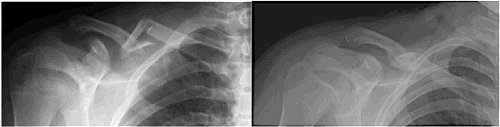

Major issues with these fractures include, in order of occurrence, pain, deformity, limited range of motion or strength, non- or mal-union (lack of healing of bony ends or poor/incomplete healing — most common in distal fractures), injury to underlying structures (blood vessels, covering of lung, lung). If the fracture fragments protrude through the skin, it is called an open fracture and has an increased risk of infection. Since the collarbone provides linkage between your sternum and your shoulder, it functions a lot like a car’s strut assembly. When your collarbone is broken, it can reduce your strength and range of motion around your shoulder joint, since it weakens that linkage.

We now know that we can be similarly effective placing the arm on the side of the fracture in a sling, instead. This is the most common method of management for middle third fractures that are reasonably well aligned. When the ends heal together, they do so by laying down additional calcium in a supportive framework that you can feel with your fingers as a lump and see on an x-ray as a bonelike mass called a callus. Yes, it is just about as strong as your bone before the break. The average time between fracture and healing to allow you to safely resume riding is six weeks. If you are thin, you may be able to see that the healed side looks a little different from the uninjured one. Since most of us are not runway models, the cosmetic abnormality is a curiosity, but not something to fix.

The current question, however, is whether the success of operative management should also be applied to all or some of the fractures that could heal perfectly well on their own. Unlike the robust data that helps us understand who should take an aspirin a day, or whether or not ongoing rider training has utility, there is not a lot of data to help decide about plating your clavicle fracture. The technique has been around for more than 20 years, but trials comparing operation versus sling have few patients and are generally limited to middle third fractures. A recent trial (ages: 5 to 21) examined less than 100 patients in total and concluded that both approaches were equivalent. Similar findings have been noted in adults in several comparisons. While new drug trials need only prove that the new drug isn’t worse than the one already in use, trials of operative techniques should demonstrate a benefit, since the operation generally includes additional risks you don't have without operation. Complications have been well described after operation, many of which, in retrospect, are believed to be avoidable.